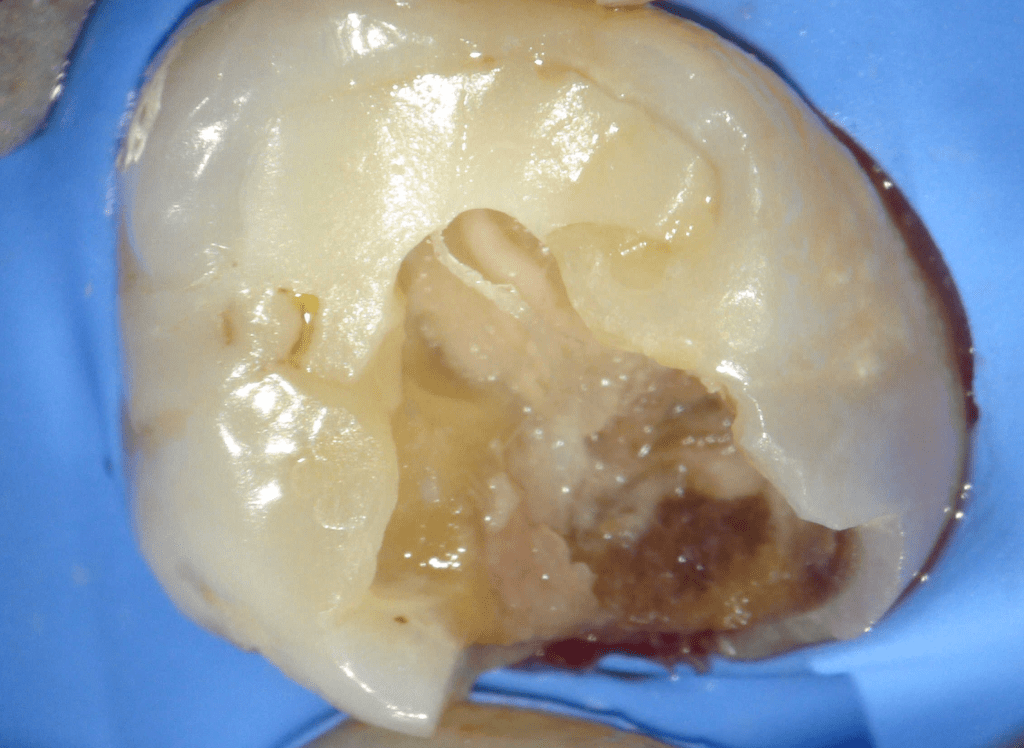

Reco pre-endo, molar inferior